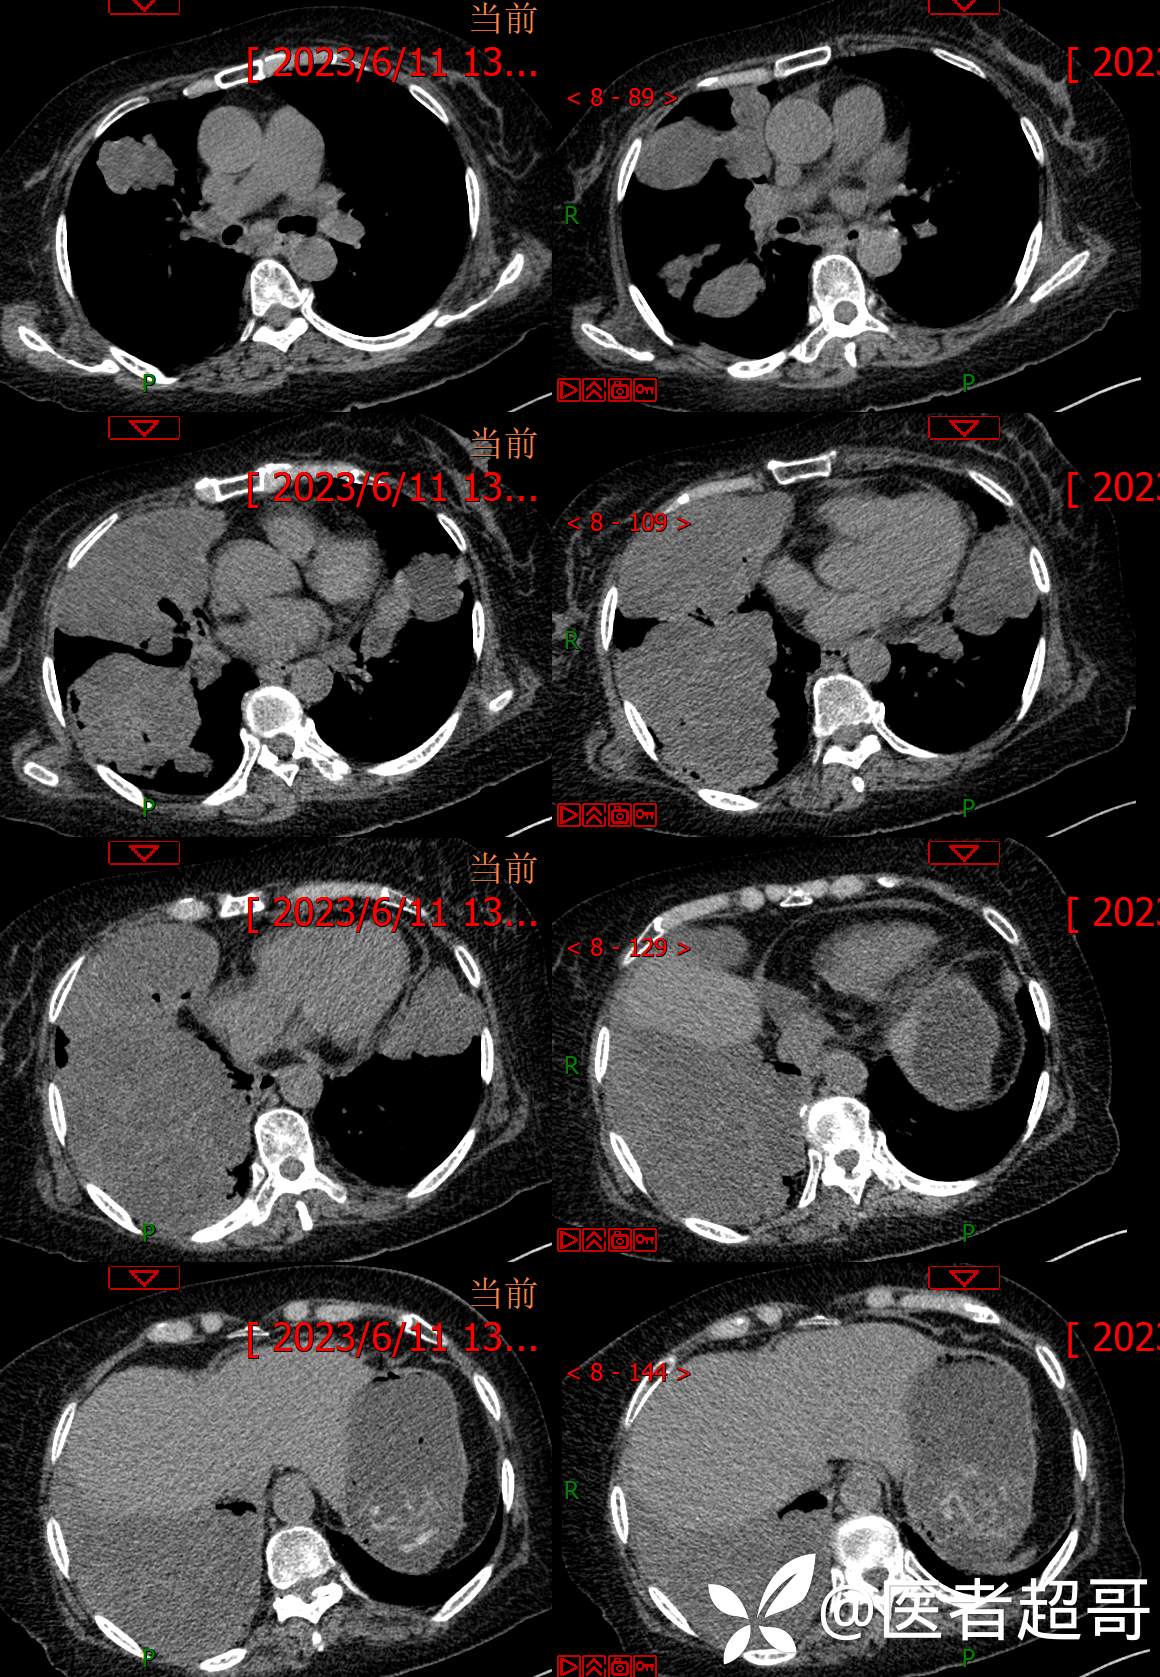

现病史:患者于4年前在神经内科住院期间监测血糖高,随机血糖29.4mmol/l,经治疗好转出院,出院诊断“锥体外系反应 2型糖尿病 感冒”,院外自行口服“二甲双胍 2片 bid,格列吡嗪胶囊 1粒 bid”降糖治疗,平素未规律监测血糖。约3年前感四肢麻木不适,无明显疼痛,无肢体活动障碍,未特殊治疗。7天前出现乏力、憋气不适,伴有流清涕,无发热、寒战,咳嗽不著,有痰不易咳出,食欲减退,无腹痛、腹泻,无恶心、呕吐,患者发病后于当地诊所就诊,监测血糖偏高(具体数值不详),给予输液治疗(具体药物不详),效果欠佳,2天前感乏力、憋气加重,今急来诊,急诊完善胸部CT平扫示:双肺多发肿瘤表现,纵膈淋巴结肿大,心包少量积液,建议三周后复查除外隐匿性骨折;血糖32mmol/l,为求进一步诊疗,门诊以“糖尿病”收入我院。

3天后增强检查视频: